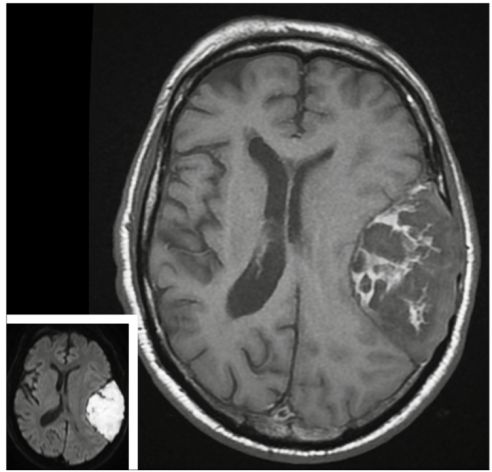

补充 MRI 如图:T1 加权病灶内部条带状高信号(主图),DWI 高信号(小图),确诊表皮样囊肿。

表皮样囊肿,胚胎期神经管闭合时因为混入了外胚层成分,逐渐生长导致的肿瘤形成。典型表现为:脑外脑池肿块,具有塑形、钻缝生长特征。

CT 一般为低密度,少数可因蛋白含量高呈高密度,囊壁可出现钙化。T1WI 通常低信号、T2WI 高信号。

DWI 弥散受限是诊断表皮样囊肿的要点,可以和颅内皮样囊肿鉴别。本例特殊性在于,影像学上能看到面积这么大的占位,但患者除了头痛之外,竟然没有出现其他显著的神经系统症状。